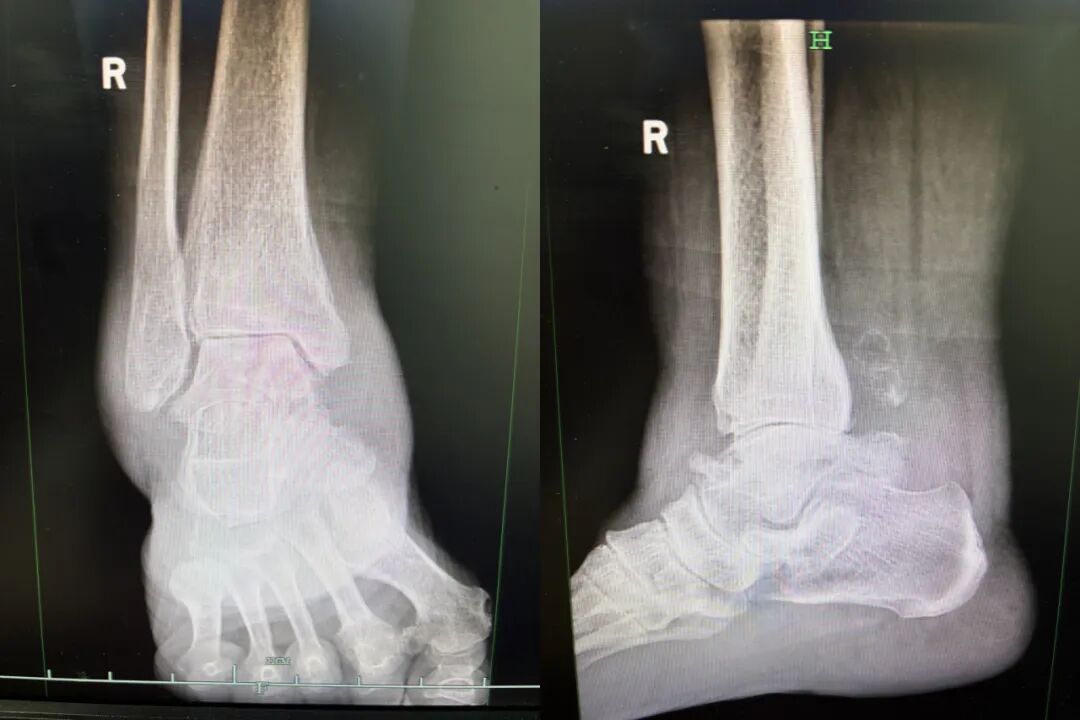

▲ 术前影像资料

右踝关节疼痛反复、走路时疼痛加重难忍,十年间,赵阿姨的生活离不开到处寻医问药,尝试了多种保守治疗方案,但疼痛与功能障碍始终未能得到有效缓解。面对医生们“建议手术”的方案,赵阿姨一家人也因为“术后万一走不了路,情况更差了怎么办”的忧虑而一直搁置。

近半年来,右踝关节的疼痛持续加重,极大地影响了赵阿姨的日常生活。在骨科主任、主任医师陈红卫的专家门诊,她表达了希望通过手术方式彻底解决问题的意愿。